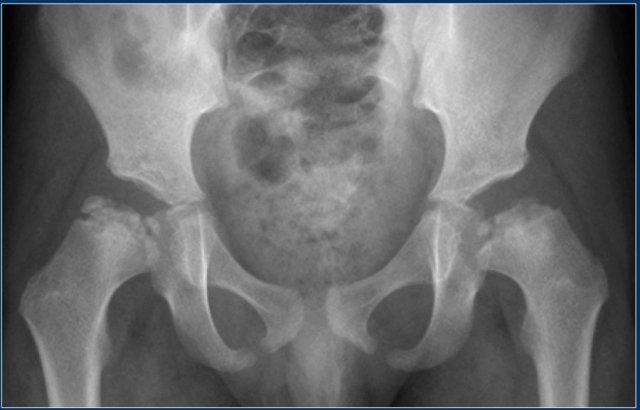

Loạn sản đa đầu xương

Loạn sản đa đầu xương có thể bắt chước bệnh Perthes vì có thể biểu hiện chủ yếu ở khớp háng.

Đây là một bệnh loạn sản xương di truyền hiếm gặp.

Bệnh nhân biểu hiện dáng đi lắc lư, đau, mệt mỏi và tầm vóc thấp.

Trái với bệnh Perthes, các bất thường thường có tính chất đối xứng.

Khớp gối, khớp cổ chân và khớp cổ tay thường cũng bị ảnh hưởng.

Quá trình cốt hóa nội sụn bất thường dẫn đến các đầu xương nhỏ, vỡ vụn kèm bất thường về trục.

Cần chụp X-quang tất cả các khớp để xác lập chẩn đoán.

Bệnh nhân sẽ phát triển thoái hóa khớp sớm.

Điều trị mang tính triệu chứng.